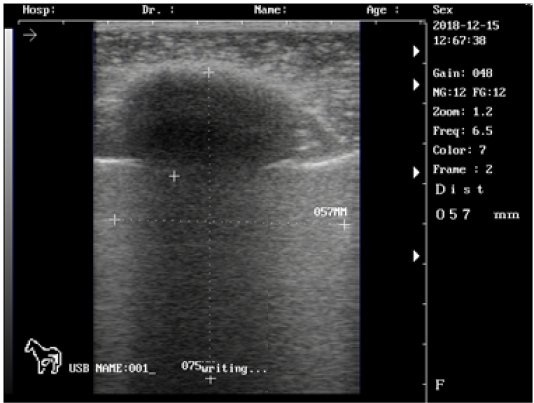

Ultrasound images of the testis of mature ram showing: high echogenicity of the testicular parenchyma; mediastinum testicular lowly echogenic